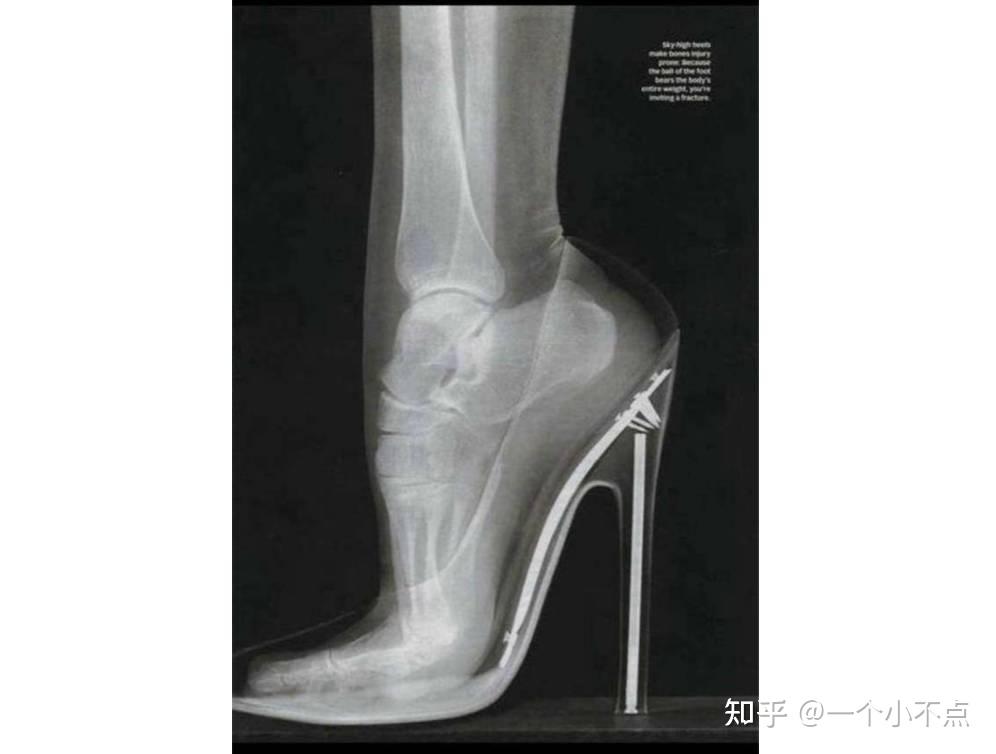

高跟鞋虽然好看漂亮,但穿起来真的很累。我们在穿高跟鞋走路的时候,原本均匀分散给脚面的力,就着重落在了脚尖上,就像是“踮着脚走路”一样,所以很容易让我们走路不稳。高跟鞋一般在正式场合穿。近来运动风潮流时尚开始流传开来,形成了当下主流的年轻时尚观,大街上到处都可以看到穿运动鞋的女生,这是一种新的时尚观念,压马路,潮就完事了。

高跟鞋太容易受伤

穿高跟鞋很容易受伤,一次也就不到一米的高台,忘了自己那是七公分的高跟鞋,就跳了下去。只听右脚嘎巴一响,眼泪立马飚了出来!脱下鞋才发现整个右脚腕肿起,眼见着就充血发黑。幸好没有伤着骨头,但是伤筋动骨一百天,每天都是一瘸一瘸度过的,老公说不要穿高跟鞋了,所以我一口气买了三双软底的休闲鞋,穿习惯了,反而觉得非常舒服,以前穿高跟鞋磨得茧子也少了很多。